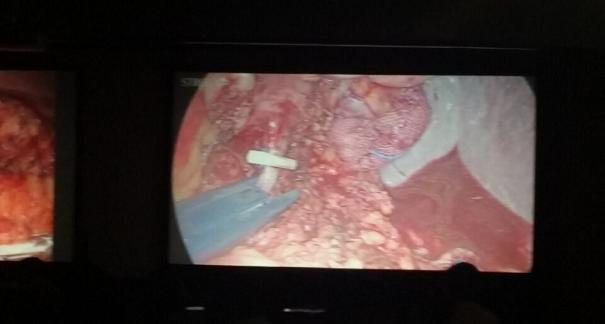

2015年10月23-25日,河北省醫(yī)學(xué)會(huì)肝膽外科學(xué)術(shù)年會(huì)在河北省石家莊市頤園賓館隆重召開(kāi)。本次學(xué)術(shù)會(huì)議河北省醫(yī)學(xué)會(huì)特邀了北京301總院的胡明根教授、天津第一中心醫(yī)院的張雅敏教授、山西醫(yī)大醫(yī)院的趙浩亮、河北醫(yī)科大學(xué)第二醫(yī)院劉建華教授等國(guó)內(nèi)知名專(zhuān)家參會(huì)。參加會(huì)議的醫(yī)院達(dá)100余家,近300名肝膽外科的臨床專(zhuān)家和一線(xiàn)醫(yī)生們親臨會(huì)場(chǎng),在此進(jìn)行廣泛的學(xué)術(shù)交流。25號(hào)全天會(huì)議安排了五臺(tái)手術(shù)視頻演示,全體參會(huì)人員進(jìn)行觀摩,并實(shí)時(shí)提問(wèn),進(jìn)行手術(shù)交流。演示手術(shù)包括腹腔鏡胰、十二指腸切除術(shù)、腹腔鏡左、右半肝切除術(shù)、腹腔鏡門(mén)脈高壓癥的治療、兩鏡或三鏡聯(lián)合膽石癥的治療、開(kāi)腹胰、十二指腸切除術(shù)、手術(shù)演示中多次使用了我公司產(chǎn)品速豐(可吸收止血結(jié)扎夾),產(chǎn)品使用滿(mǎn)意度受到專(zhuān)家們的一致好評(píng)。